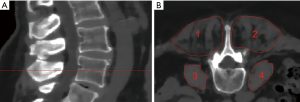

Segmentation of the psoas muscle and the erector spinae and muscle density (MD) measurements

The psoas muscle and the erector spinae muscles were segmented bilaterally at the level of L4 over a craniocaudal distance of 10 mm in the axial reformations of the original dose images (Figure 1). Segmentation was performed by using the free open-source software Medical Imaging Interaction Toolkit (MITK, developed by the Division of Medical and Biological Informatics, German Cancer Research Center, Heidelberg, Germany) by a radiologist with 4 years of experience. Segmentations were superimposed on all low-dose scans. MD was extracted in Hounsfield Units (HU) of each muscle in each scan. Volume weighted mean MD of the right and left psoas and erector spinae muscle was calculated, respectively. A second reader performed segmentation of all included subjects to evaluate the inter-rater reliability of the results.